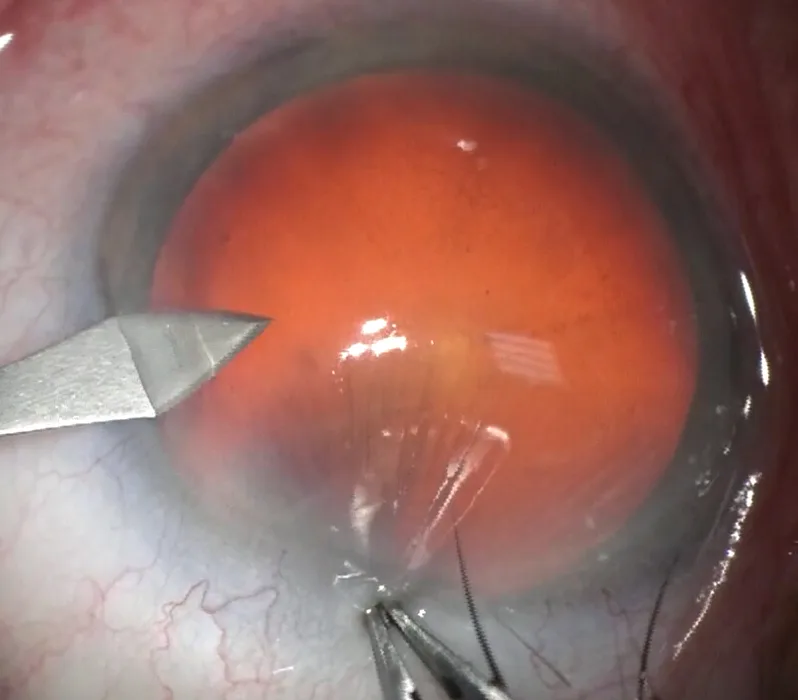

Figure 3.3. Incision cornéenne construite en trois temps. Troisième phase ici : ouverture descemétique complétée sur 1,8 mm.

Construction

L’incision principale peut être directe – en un seul plan ( vidéo 9 , cas 6 ) – ou bien construite en deux ou trois plans ( figure 3.6 et vidéo 9, cas 5 ). L’incision principale construite semble avoir aujourd’hui gagné la faveur de la majorité des chirurgiens. En pratique, la création de la première lèvre se fait de façon orthogonale – avec le couteau utilisé pour l’incision principale ou bien un couteau pointu de 15°, 30° ou 45° dédié – sur un tiers de l’épaisseur de la cornée, puis le tunnel et la lèvre interne sont réalisés ( figure 3.7 ).

La construction axiale en trois plans, les deux premiers plans étant les plus déterminants, présente essentiellement deux avantages :

la réalisation d’un toit externe solide qui résistera mieux aux entrées et sorties des instruments, garantissant une berge externe saine en fin de chirurgie ;

la cohésion naturelle des versants internes et externes après la chirurgie, gage d’étanchéité postopératoire et donc de sécurité, en termes de mouvements postopératoires de chambre/d’implant, et de prévention de l’endophtalmie en évitant les flux liquidiens rétrogrades.